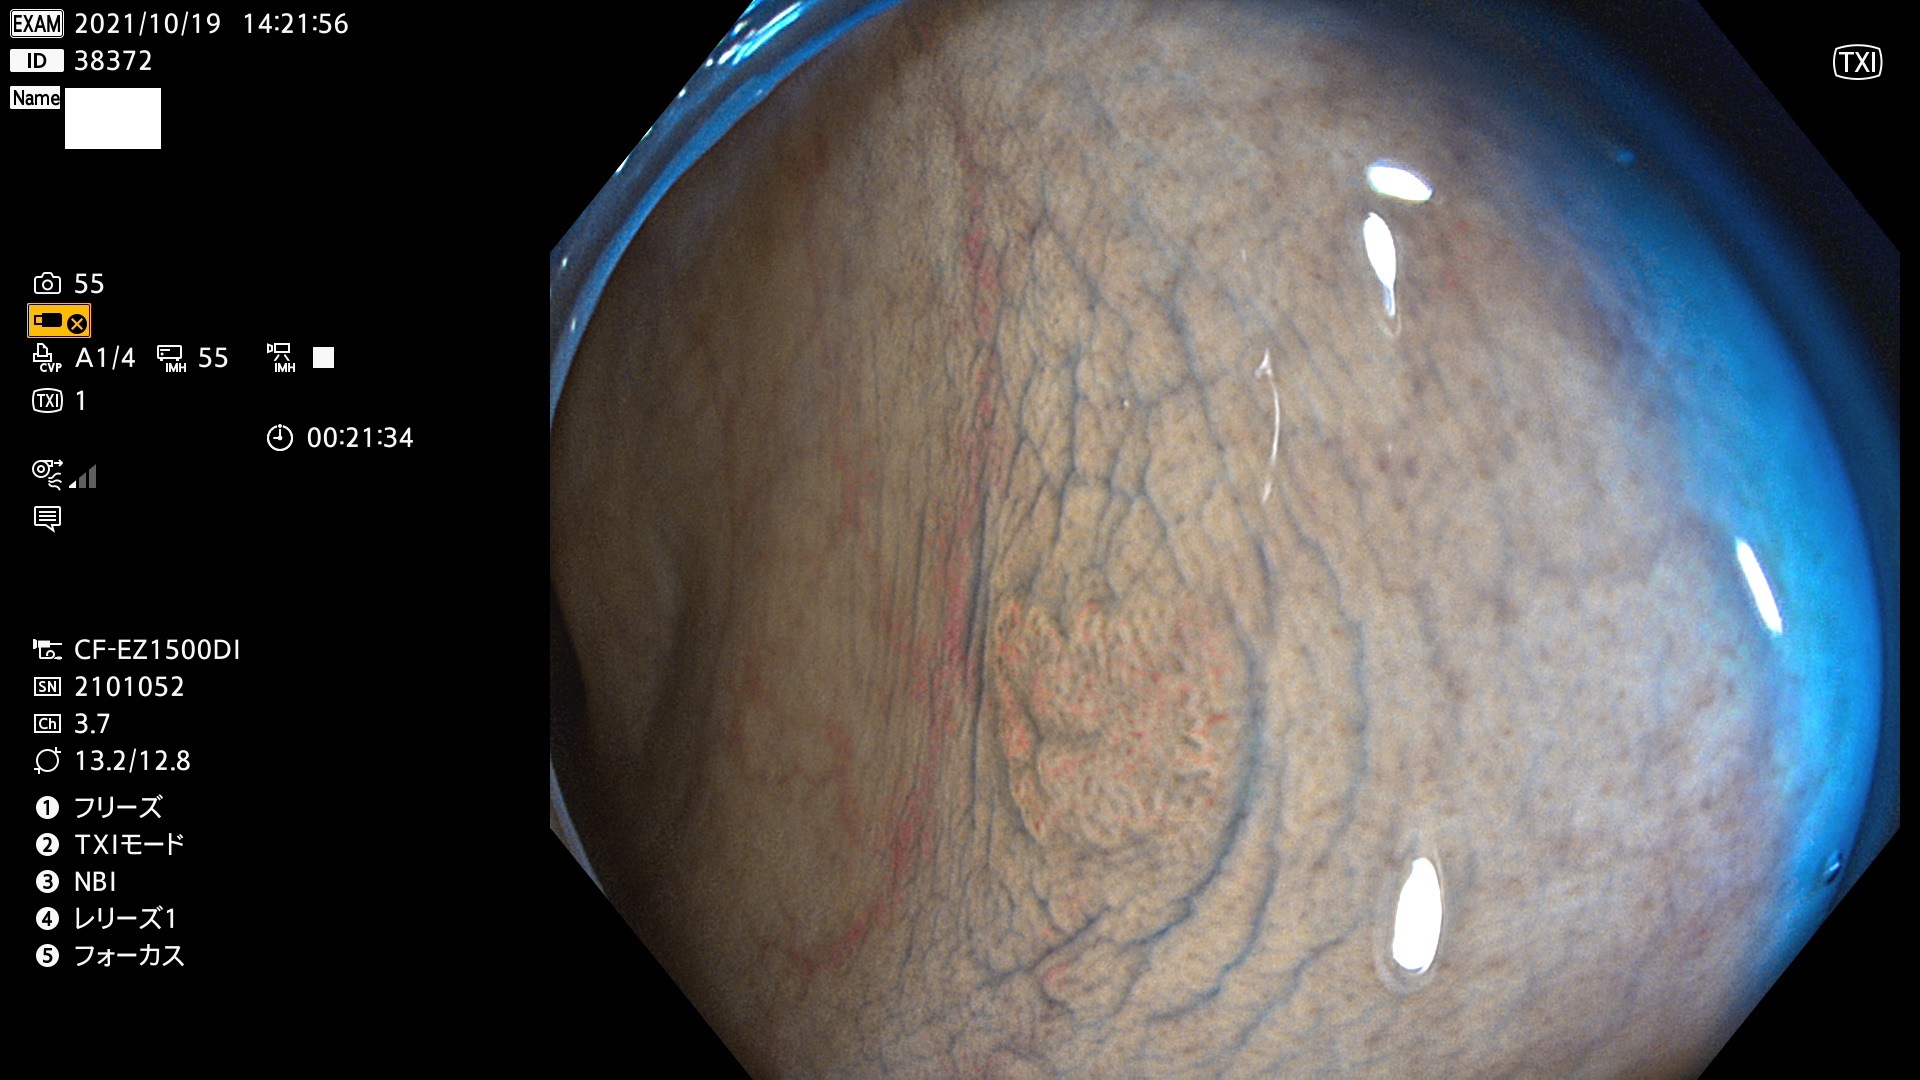

38300 38301 38302 38303 38304 38306 38307 38308 38309 38310 38311 38312 38313 38314 38315 38316 38317 38319 38321 38322 38323 38324 38325 38327 38331 38332 38333 38334 38337 38338 38339 38340 38341 38343 38346 38348 38349 38350 38351 38352 38353 38354 38355 38358 38359 38360 38361 38362 38363 38365 38366(SSAP) 38368 38369 38370 38371(SSAP) 38372 38374 38375 38376 38377 38378 38380 38381 38382 38383 38384 38385 38386 38388 38389 38391(SSAP) 38395 38397 38399

発見困難で危険性の高い平坦型病変(上記100名より抽出)